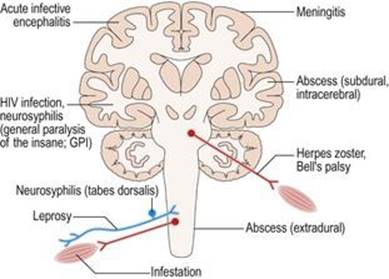

التهاب بافت عصبی عضلانی ممکن است ناشی از عفونت توسط میکروارگانیسمها باشد (شکل ۱.۳۸) و میتواند ساختارهای مختلفی را تحت تاثیر قرار دهد: به عنوان مثال مننژها (مننژیت مننگوکوکی)، مغز (آنسفالیت ویروسی، نوروسیفلیس) یا اعصاب محیطی (جذام). متناوبا، التهاب میتواند در اختلالات ایمنی رخ دهد (شکل ۱.۳۹)، در غیاب عفونت. شایع ترین اختلال سیستم ایمنی CNS، مولتیپل اسکلروزیس است. اختلالات ایمنی ممکن است به اعصاب محیطی نیز ضربه بزند (نوروپاتی التهابی حاد یا سندرم گیلن – باره).اتصال عصبی عضلانی (میاستنی گراویس) یا ماهیچه (پلی میوزیت). اختلالات التهابی با آزمایشات میکروبیولوژیکی و سرولوژیکی خون و CSF بررسی میشود. درمان عفونت با عوامل ضد میکروبی و سرکوب پاسخهای ایمنی توسط داروهایی مانند کورتیکواستروئیدها ممکن است این بیماریهای عفونی یا ایمنی را درمان یا کنترل کند.

شکل ۱.۳۸ عفونتهای سیستم عصبی عضلانی.

شکل ۱.۳۸ عفونتهای سیستم عصبی عضلانی.

شکل ۱.۳۹ اختلالات ایمنی سیستم عصبی عضلانی.

شکل ۱.۳۹ اختلالات ایمنی سیستم عصبی عضلانی.